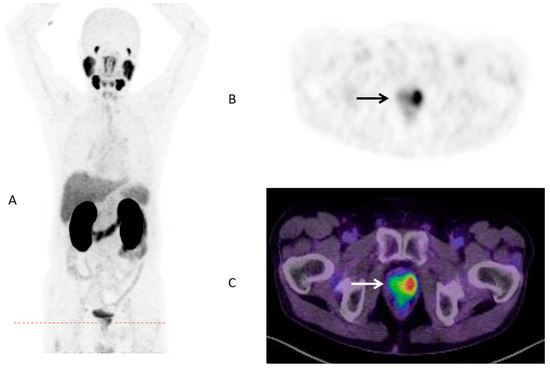

Until now, the identification of patient subgroups suitable for treatment escalation leading to improved survival is still challenging. Although numerous pretreatment risk stratification tools like the Memorial Sloan Kettering Cancer Center (MSKCC) nomogram or the Cancer of the Prostate Risk Assessment (CAPRA) score are available [27], there is a lack of evident data with regard to individual therapeutic consequences. Increasing numbers of PSMA-PET/CTs for primary staging around the globe confirms a great potential to that molecular imaging methodology. As published a few years ago, SUVmax of intraprostatic, malignant lesions was highly correlated with several clinical parameters like Gleason Score (GS) or PSA [28]. The present study observed a statistically significant higher SUVmax for men with metastatic disease (Figure 2 and Figure 3).

Figure 2.

PSMA-PET/CT in maximum intensity projection (MIP) (A) of a 70-years old patient with prostate cancer (GS 7b/group grade 3, PSA 4.53 ng/mL) and low intraprostatic SUVmax (3.45) and no metastases (B) PSMA-PET Dx; (C) PSMA PET/CT Dx.

Figure 3.

PSMA-PET/CT in MIP (A) of a 83-years old patient with prostate cancer (GS 8/group grade 4; PSA 32 ng/mL) and high intraprostatic SUVmax (49.63) and several metastases; Level of prostate (B) PSMA-PET Dx; (C) PSMA PET/CT Dx; Level of nodal metastases (D) PSMA-PET Dx; (E) PSMA PET/CT Dx.